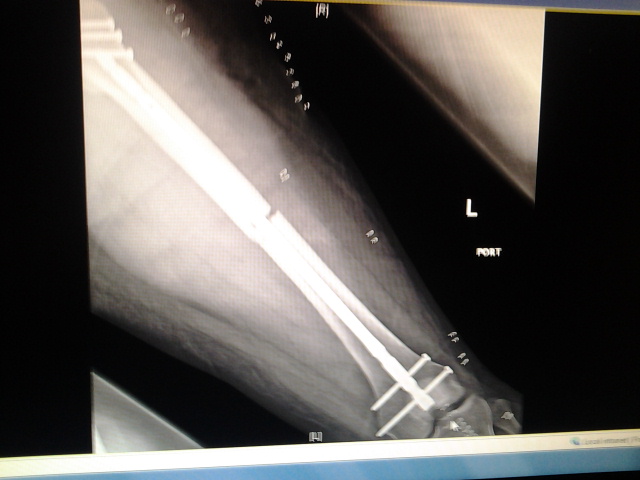

So... To start, I had a motorcycle accident and broke my leg in two places. They had to insert a rod and a bunch of screws in. But I think I had nerve damage. How I know? Well the outside of both my legs to the small toes are numb. Not totally, I have feeling. But they're numb.

I had the accident on 4-7-14. Been non-weight bearing on my left leg since.

Attachment:

2014-04-10 08.08.20.jpg

2014-04-10 08.08.20.jpg [ 84.72 KiB | Viewed 5416 times ]

Just don't ask me how my bike fared :/